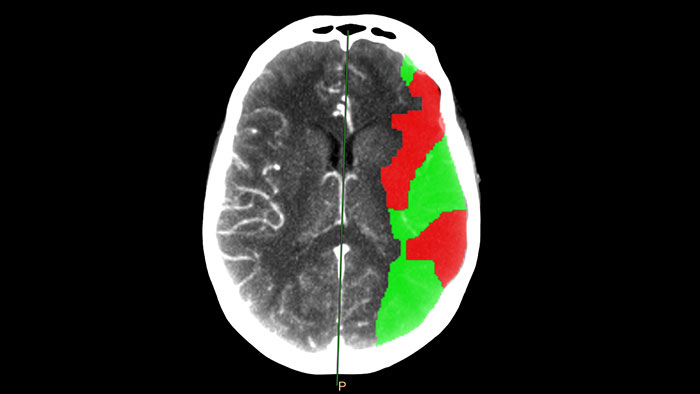

Determine areas of reduced cerebral blood flow as compared to the contralateral hemisphere

Generates qualitative and quantitative information about changes in image intensity over time. The application calculates and displays quantitative color maps of cerebral blood flow (CBF), cerebral blood volume (CBV), mean transit time (MTT) and time-to-peak (TTP), and provides summary maps which may help physicians in determining areas of reduced cerebral blood flow compared to the contra lateral hemisphere.